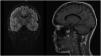

Papilledema was ruled out and the evaluation completed with head CT and MRI scans (Fig. 1). Based on the imaging findings, the principal diagnostic impression was diffuse midline glioma, although an inflammatory process could not be ruled out. This prompted extension of the evaluation with magnetic resonance spectroscopy (MRS), the findings of which were inconclusive for diagnosis of a tumor (Fig. 2). The surgical biopsy was deferred to perform a 11C-methionine PET scan, the findings of which were not suggestive of high grade glioma. Suspicion of autoimmune encephalitis prompted testing for anti-MOG/AQP4 antibodies (which turned out negative) and initiation of intravenous steroid therapy.1